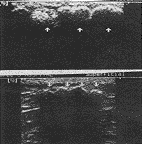

中国超声医学杂志990525 例1 患者女,65岁。因左髂部包块14年就诊,查体:左髂部皮下触及7.0cm×4.0cm×2.0cm的包块,质硬,有结节感,可活动。应用美国HP Image Point彩色超声诊断仪,探头频率7.5MHz,超声所见:左髂部皮下脂肪层内探及范围7.5cm×3.4cm×1.5cm的强回声区,呈结节状,后方伴声影(图1,上)。探查右侧同一部位亦见0.7cm×0.4cm的强回声,与左侧包块回声特征相同。CDFI:包块内部及周围未见血流信号。超声诊断:双侧髂部皮下脂肪钙化。

例2 患者女,22岁。因臀部肿物一年就诊,查体:左臀部偏上方皮下触及5.0cm×2.0cm的包块,质硬,表面不平。右臀部同一部位见2.0cm×1.0cm的包块,性质同左侧。超声所见:左侧臀部偏上方脂肪层内见一4.9cm×2.0cm的波浪状强回声,后方有明显声影(图1,下),右侧臀部脂肪层内亦见一强回声区,大小1.8cm×1.4cm,回声特征同左侧。CDFI:内部及周围均未见血流信号。

图1 骨化性脂膜炎